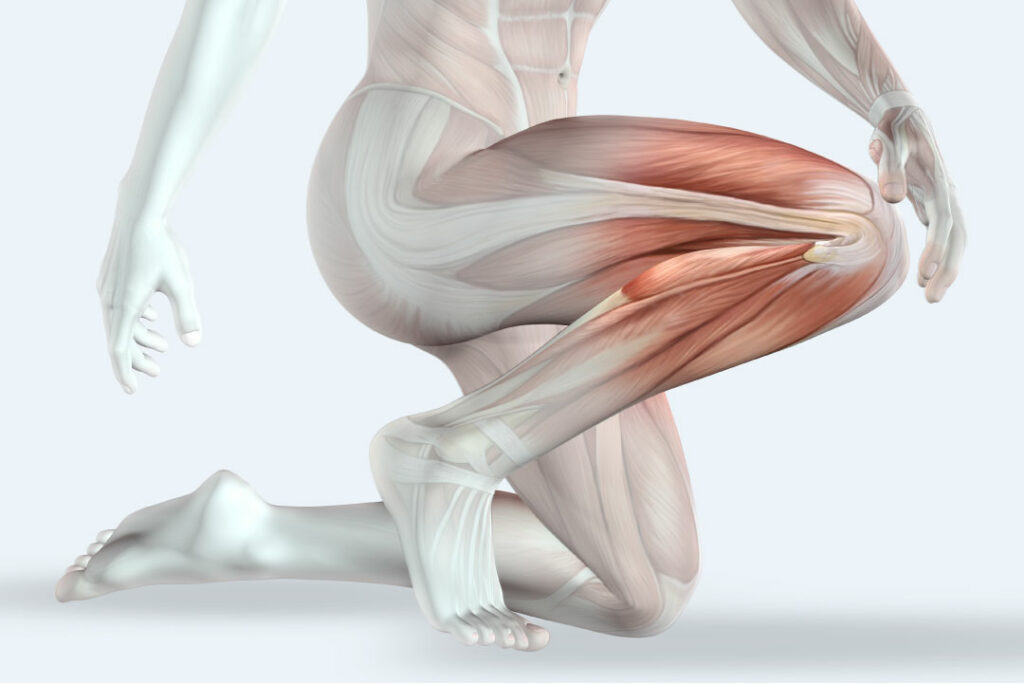

There’s more to your joints than your joints

While osteoarthritis is common, there are lots of other causes of joint pain. Tough, non-stretchy bands called ligaments help keep your joints in place. Your knees are also supported by muscles which protect your joints from damage. You can’t strengthen your ligaments, but you can certainly give your muscles a helping hand with regular aerobic exercise – the kind that makes you mildly out of puff. This can be particularly helpful in avoiding knee problems. The knee carries the whole weight of your body and is exposed to all sorts of strains every time you move your legs. Isometric exercises – lifting your leg with your knee straight, to prevent any strain on the joint – can let you exercise the muscles even if you’ve been told to avoid too much bending under pressure.